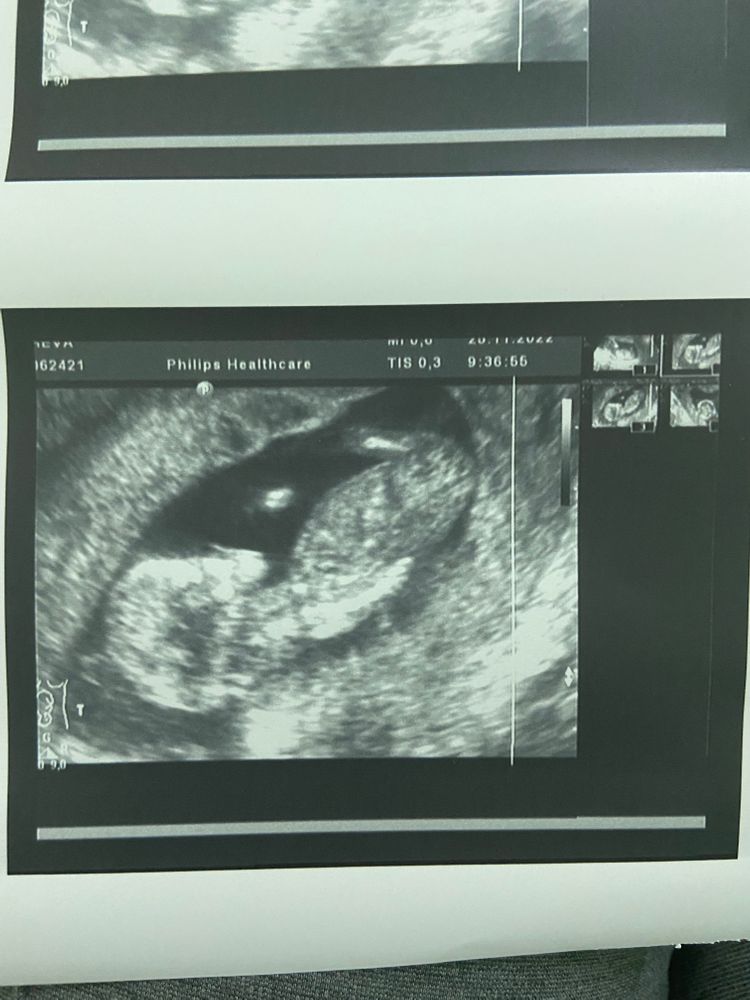

Половой бугорок ))

Девочки, погадаем на кофейной гуще? Узист была принципиальная и не сказала, хотя увидела пол 😭 у меня сыночек 1.3 года. Так Интересно , погодки будут мальчики или мальчик и девочка )

А где бугорок?👀 я ножку вижу

Так бугорок за ножкой.. а так, отлично уже сейчас видно по бугорку, кто будет у вас. Жаль других фото нет..(

♥ Ангелочек ♥, ага, я просто надеялась что это дальняя ножка и бугорок между ними, а теперь вижу что это ближняя, правая ножка.

Виктория, так да... ножка, а бугорок не спереди неё?

короче, фотка не подходит да ?

Ляля, если это принять за бугорок, то смотрит он слишком вверх, у девочек же вроде должен идти параллельно?